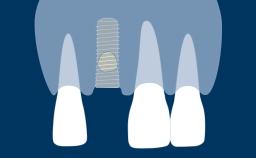

Timing of Implant Placement after Tooth Extraction

Learning Module

Early (Delayed) Placement of Implants

Congress Lecture